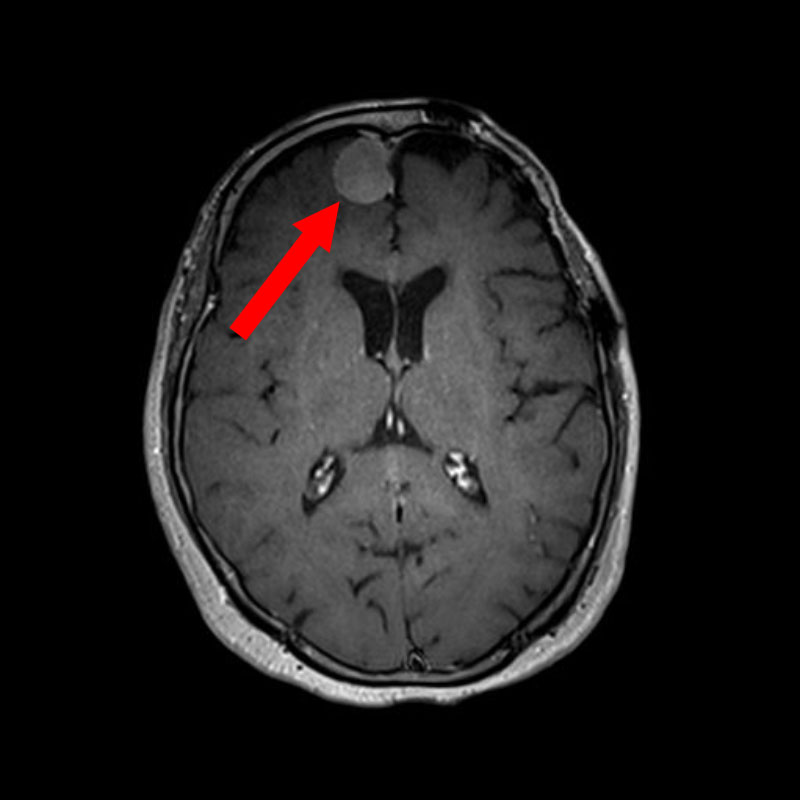

No.’25_108 手術前1

No.’25_108 手術前2